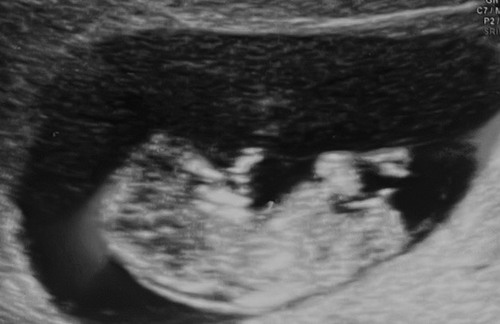

Is hier een NUB op te zien?

Helaas niets te zien. Hoeveel weken ben je hier?

Reactie op saartje221122

10+3

En op deze ook niet?

Nee sorry, niet te zien